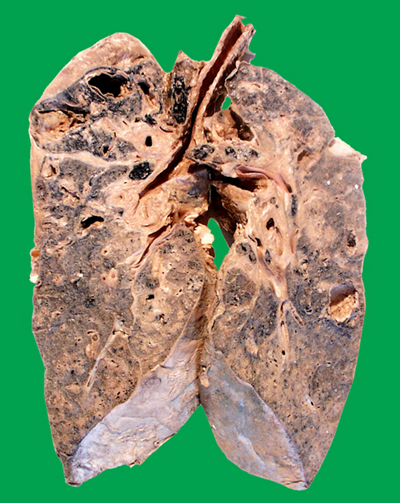

肺結核圖片